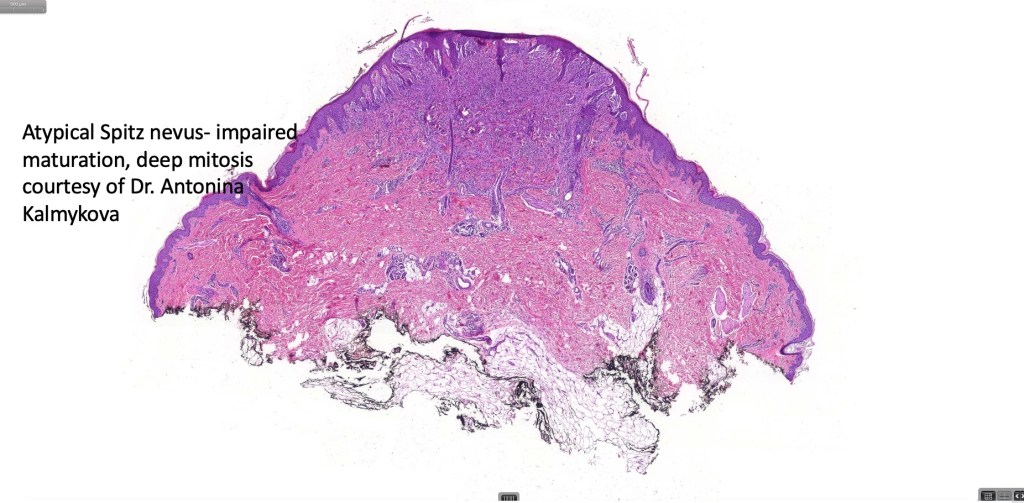

Atypical Spitz nevus/tumor

The term atypical Spitz nevus/tumor was introduced as a means of separating out those lesions which show features of a Spitz nevus with some but not all of those seen in melanoma. It implies diagnostic uncertainty. While the reason for its introduction is laudable, the term has been inappropriately abused by some for any Spitz nevus showing the slightest deviation from the classical features. The term has turned into a dumping ground particularly for the inexperienced. Although not completely true, the statement by the late Bernie Ackerman that “atypical Spitz nevus comprises an admixture of Spitz nevi and melanoma” with nothing else has merit. The term should not be applied lightly as it is certainly associated with risk of sentinel node spread & sometimes beyond. I have never been keen on the entity. While I agree that not all cases are readily characterized as benign or malignant, I do believe that the over whelming majority of cases can and should be. I used to tell the residents and fellows the following potted history. A patient was noticed by his/her partner to have an odd pigmented lesion on the back. The patient went to the general practitioner who agree that it was odd and arranged for a dermatology referral. The dermatologist also thought that it was odd and excised it. The pathologist agreed that it was odd but didn’t know if it was benign or malignant. The patient and his/her partner wondered why they has bothered worring about it in the first place!

The advent of the molecular era has resulted in the re-classification of many of these lesions. Features which are often used in the diagnose of atypical Spitz nevus include:

Impaired circumscription and asymmetry

Imapired maturation

Deep mitoses,